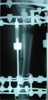

Post

Op

Varus deformity over distraction site

Post-op 2nd surgery :

Acute correction with IM nailing

Progress

Deformity corrected with 150degrees knee motion